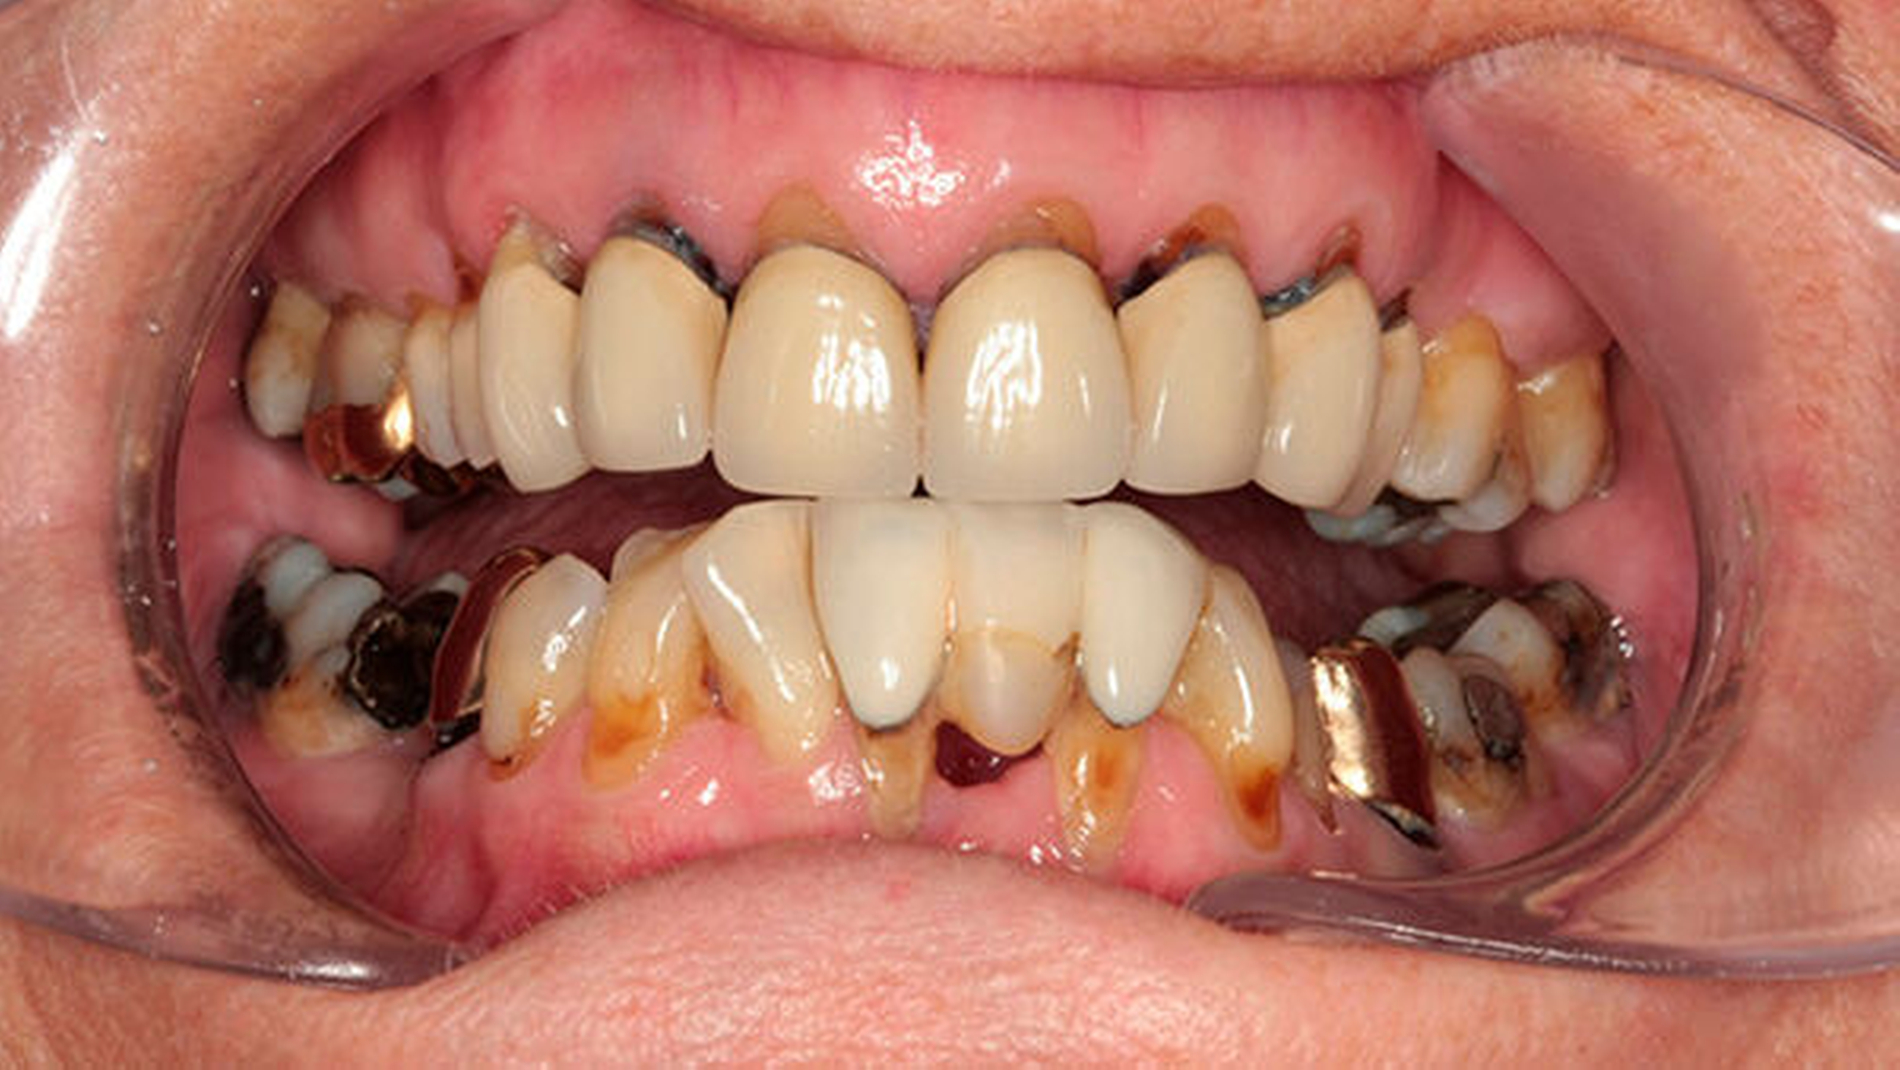

Dazu gehören das Auftreten von dünnen und verletzlichen Schleimhäuten der Mundhöhle, die fehlende Bildung eines Speichelsees im Mundbodenbereich, die aufgrund der fehlenden Selbstreinigungsfähigkeit der Mundhöhle vermehrte Ablagerung von Plaque sowie schließlich das Auftreten von kariösen Läsionen insbesondere im Zahnhalsbereich, die letztlich zu Frakturen führen können (Abbildung 2). In diesem Stadium gestaltet sich die restaurative zahnärztliche Therapie oft sehr schwierig. Weiterhin treten vermehrt Rhagaden der Mundwinkel auf. Bei besonders ausgeprägter Mundtrockenheit im Zuge strahlentherapeutischer Behandlungen werden häufig foudroyante Karies und Foetor beobachtet.